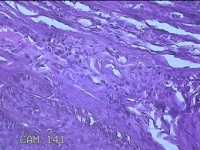

左眼外侧缘上肿物

性别

女

年龄

60岁

临床诊断

痣;疣

左眼上睑缘白色丘疹1年余。

灰白粉红色肿物0.8x0.3x0.2cm两个,表面光滑。

图4